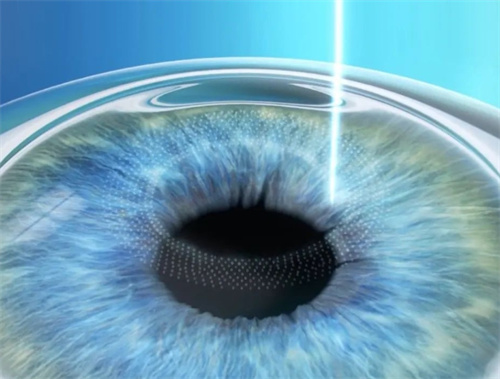

全飞秒激光手术:15800元/双眼